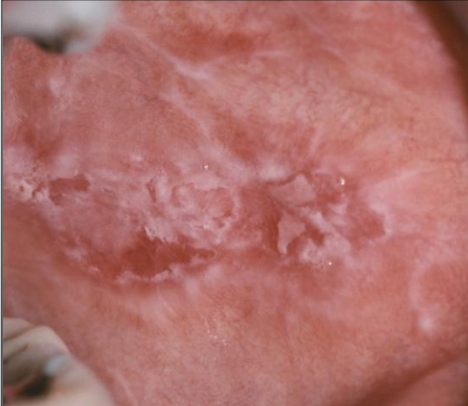

White lace-like striations (Wickham striae), maybe erythematous, bleeding

What is reticular lichen planus?

More common, asymptomatic, lace-like (Wickham striae)

What is erosive lichen planus?

Not as common, painful, erythematous, bleeding